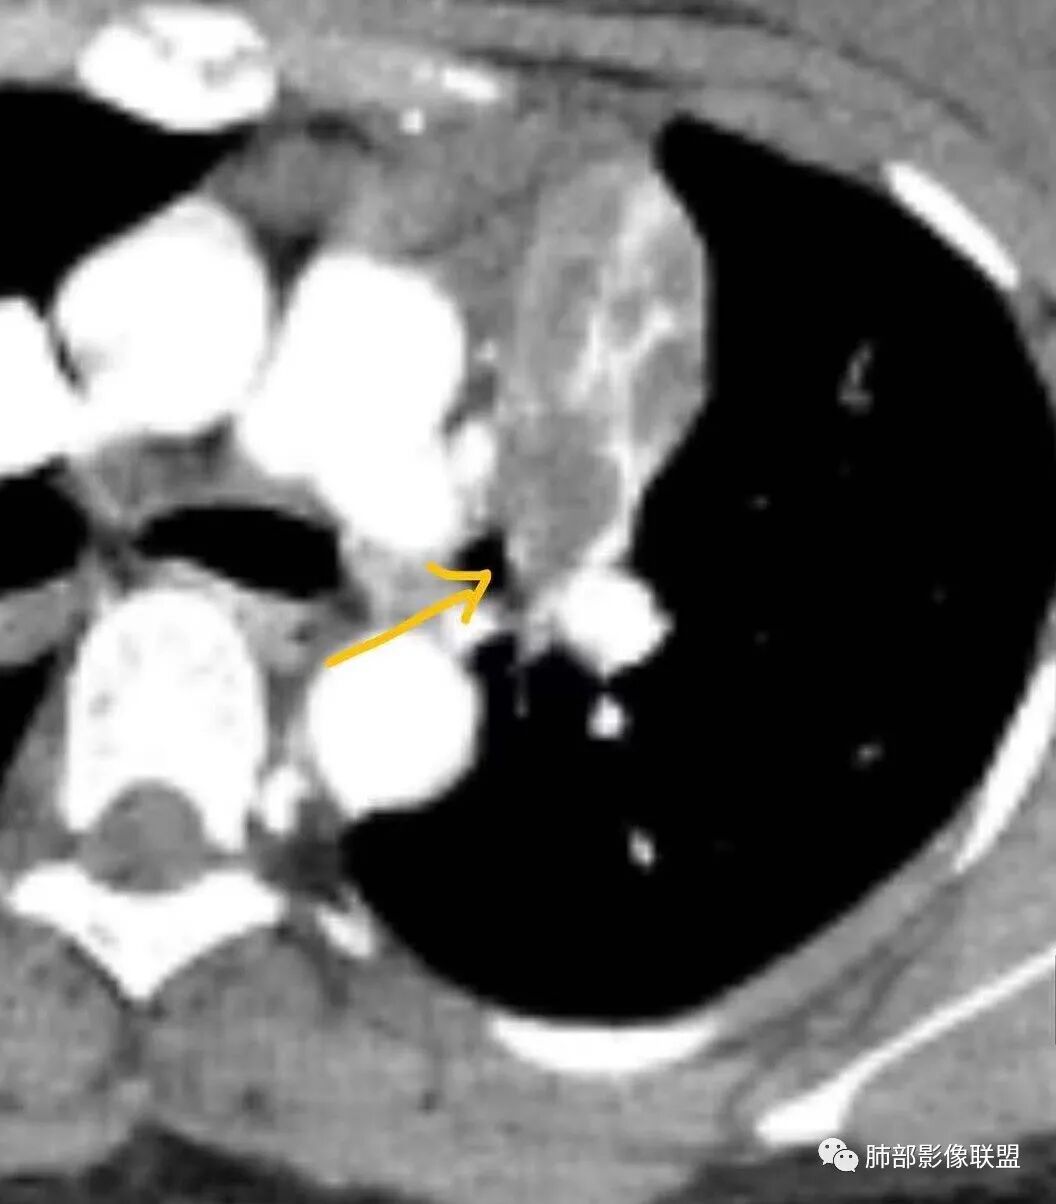

年轻女性,咳嗽咳痰一个月,左肺体积缩小,左肺尖部胸膜下实变影,宽基底与胸膜相贴,病灶边缘平直收缩,部分略膨隆,病灶下方可见支气管挤压,肺窗所示:周围伴有多发结节部分可见树丫征,纵隔窗可见病灶与纵隔胸膜黏连,部分与左肺动脉分界欠清,平扫密度尚均匀,增强扫描不均匀强化,内部可见多个低密度坏死,伴有条状血管影,纵隔淋巴结略有肿大。

胸部CT:左肺体积缩小,左肺上叶前段纵隔旁胸膜下大片实变影,边缘清楚、匀齐、平直收缩,部分略膨隆,周围多发结节、树芽卫星灶,纵隔窗病灶与纵隔胸膜黏连,实变内多发点状钙化。平扫密度尚均匀,增强扫描不均匀明显强化,多个低密度区,呈仙人掌样,伴有条状血管影,考虑慢性炎症伴左上叶前段支气管闭塞,TB?鉴别黏表、腺癌等。

青年女性,咳嗽、咳痰、痰中带血1月余,左肺上叶纵隔旁团片影,边缘见平直、U型凹陷,边缘以收缩为主,部分膨隆,内有点状钙化,增强见支气管粘液栓,病灶近端见坏死。周围少许小点状影(考虑卫星灶可能),首先考虑结核,鉴别粘表。